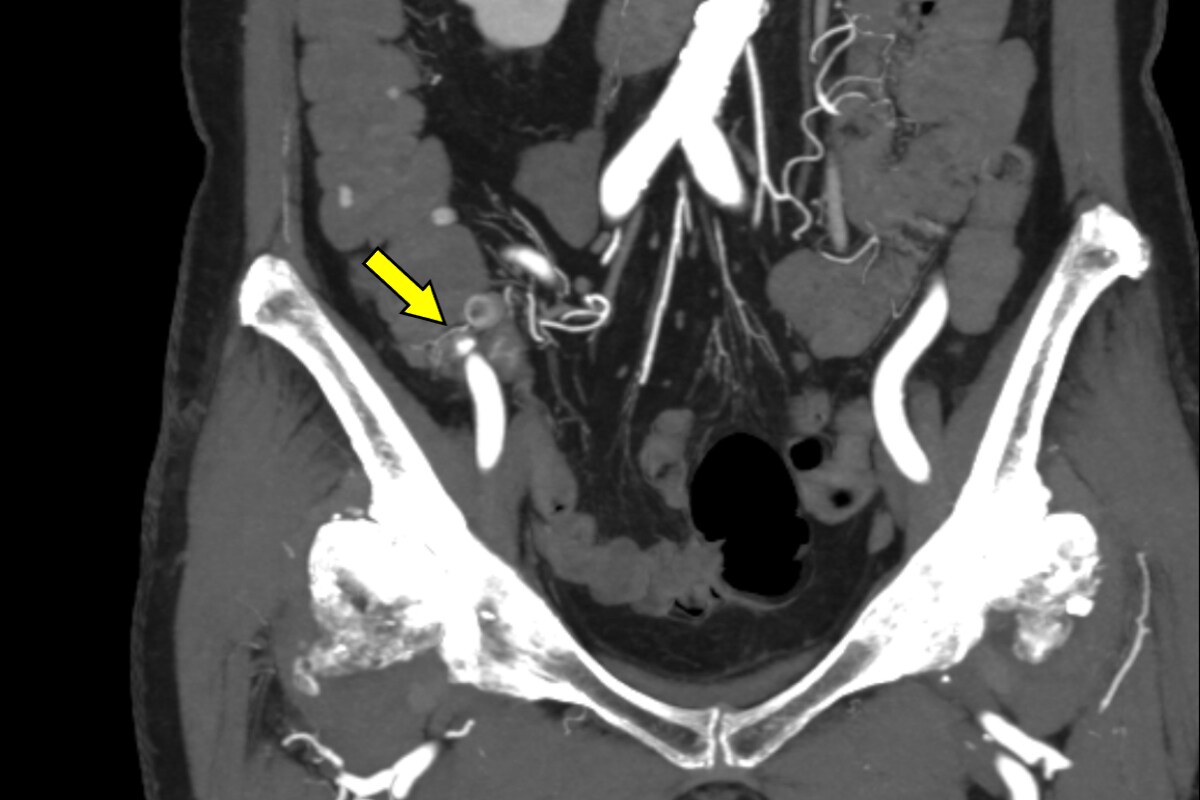

血便があり、当院消化器内科に入院となった。第3病日に下部消化管内視鏡を行うも出血源は不明であった。第4病日に再度血便があり、造影CTを施行すると上行結腸憩室からの活動性出血を認めたため、速やかに緊急TAEを施行した。血管造影で回結腸動脈の分枝からextravasationを認め、責任動脈をコイル塞栓した。術後、再出血、Hb値の低下を認めず、第13病日に退院となった。

消化管出血では出血源を迅速かつ正確に同定することが診療上、不可欠である。内視鏡は有用であるものの、腸管の前処置を要し、観察に時間を要する他、出血が間欠的であれば診断が困難となる場合がある。これに対して造影CTは、非侵襲的かつ短時間で活動性出血の有無と局在を明確に描出できる。活動性出血があれば、動脈相から腸管内への造影剤の漏出を認め、静脈相や遅延相ではその造影剤漏出の拡大を確認することで、客観的に活動性出血を診断できる。さらに、造影CTで得られた情報に基づき責任血管を同定することで、後続の血管造影検査の効率が高まり、速やかに経カテーテル的動脈塞栓術(TAE)へと移行できる。当院では、造影CTで活動性出血が確認された結腸憩室出血に対して速やかにTAEを施行しており、その成功率向上に寄与している。一方で、出血が間欠的または少量の場合には描出が難しく、検査のタイミングによって診断能が左右されるという限界もある。それでも、結腸憩室出血において造影CTは診断と治療方針をつなぐ、重要な検査として位置付けられる。

本症例ではPhoton Counting CT(PCCT)を用いた。PCCTは従来型CTに比べ空間分解能とコントラスト分解能が高く、少量の造影剤でも高精細な画像を得られることが特徴である。これにより微細なextravasationやそれに連続する責任動脈の描出が可能となり、診断精度を大きく高める。

PCCTによる高精細な画像はextravasationの検出にとどまらず、責任血管を描出することで標的血管の特定を容易にする。その結果、血管造影での探索時間が短縮され、経カテーテル動脈塞栓術(TAE)の迅速かつ確実な施行につながり、手技の成功率と効率を高めている。